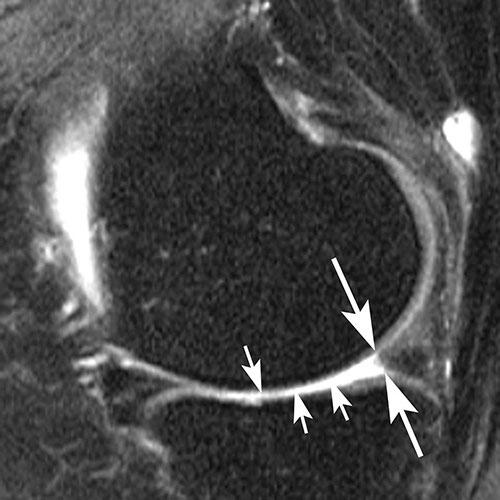

Sagittal intermediate-weighted fat-saturated image shows a typical horizontal-oblique meniscal tear of the posterior horn reaching the undersurface of the meniscus (arrows).